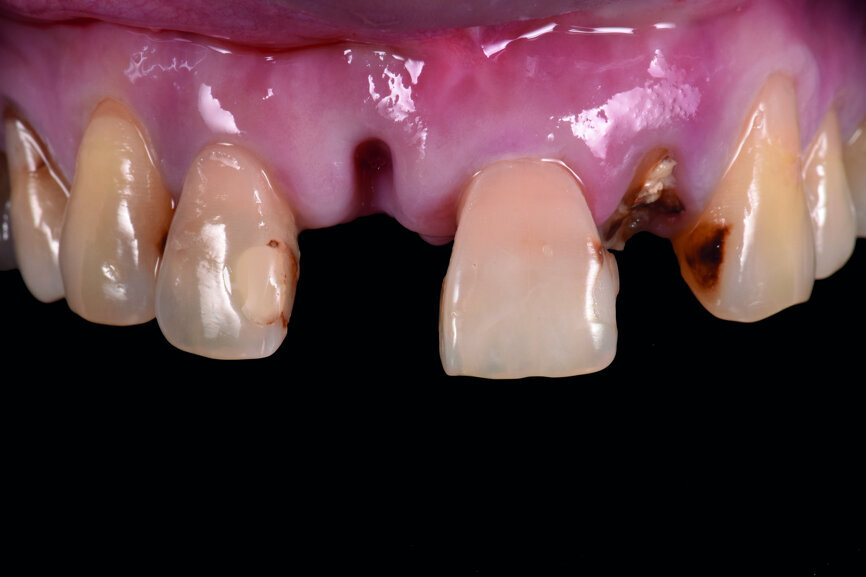

A 40-year-old female patient had sustained trauma to her anterior teeth caused by accidental syncope three weeks before. The clinical examination found that tooth #11 had been luxated; the crowns of teeth #12 and 21 had fractured, with the residual margin extending 3–5 mm below the gingiva and the teeth affected by Grade III mobility; and the crown of tooth #22 had fractured, with the residual margin at gingival level. There were no obvious abnormalities in the remaining teeth (Figs. 1–4). After excluding major systemic diseases, it was decided that she required fixed implant restoration with high demands regarding aesthetics and function.

Fig. 1: Pre-op frontal view of the anterior teeth.